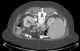

Benign symmetric lipomatosis is a skin condition characterized by extensive symmetric fat deposits in the head, neck, and shoulder girdle area. The German surgeon Otto Wilhelm Madelung was the first to give a detailed description of the disorder. [Source: Wikipedia ]

Diffuse lipomatosis of the neck

Lipomatosis

Benign symmetric lipomatosis